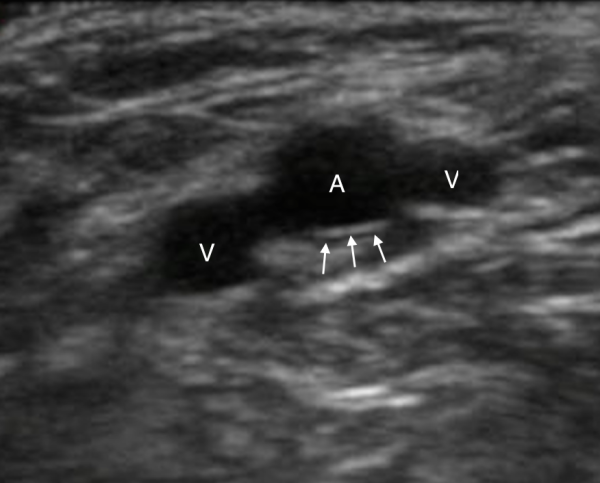

Figure 2. An artery (A) will have thicker, hyperechoic walls (arrows) when compared to veins (V). Image Courtesy of Sierra Beck, MD and Bradley Wallace, MD